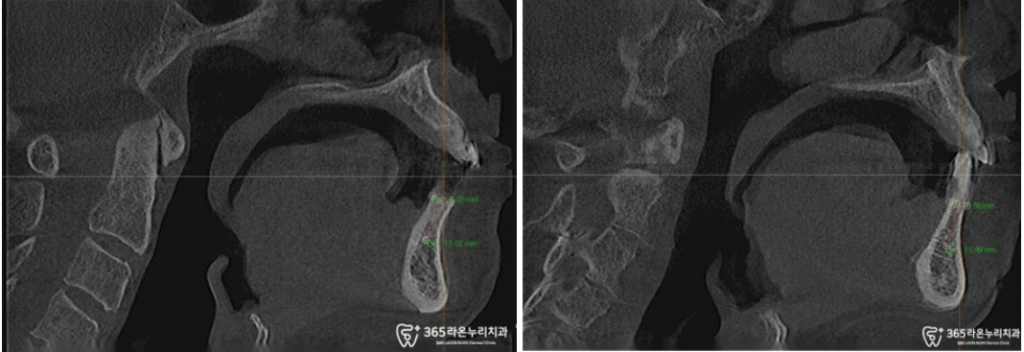

치료 전, CT로 남아 있는 뼈의

상태 확인도 잊지 않았습니다.

왼쪽 위턱의 뼈 양을 확인하고,

상악동 거상술로 임플란트 픽스처가

들어갈 공간 확보 및 뼈이식 과정을 함께

진행해드렸습니다!